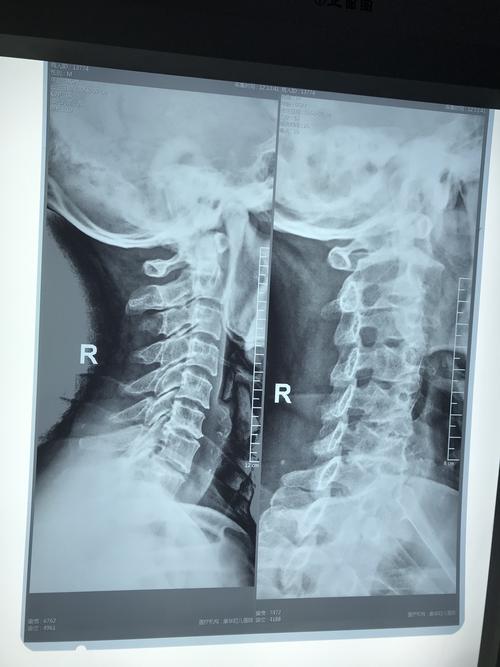

新手看颈椎ct片图解

颈椎x光片讲解

颈椎x光片